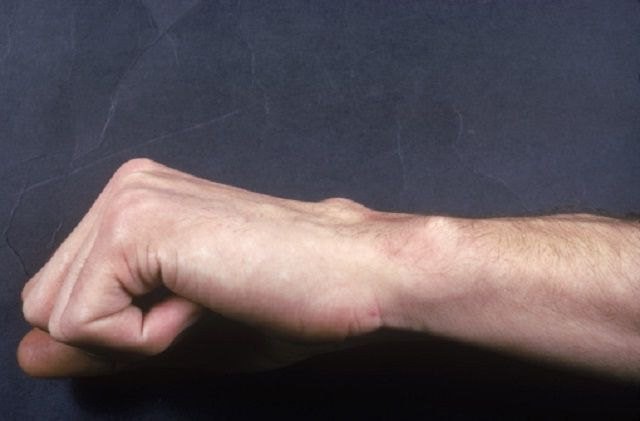

Субхондральный остеосклероз – самая распространенная разновидность уплотнения ткани. Это одно из основных проявлений таких заболеваний опорно-двигательного аппарата, как остеохондроз и артроз. Уплотнение костей происходит на границах с пораженными воспалительным процессом участками. Областью его поражения становится позвоночник, чаще всего шейный и поясничный отделы, и суставы – коленные, тазобедренные, пальцев рук.

Сам термин субхондральный означает «подхрящевой». Костная ткань под поврежденным хрящом уплотняется, разрастается, со временем образуются наросты – остеофиты. В начальной стадии они себя не проявляют, в тяжелой форме вызывают боли при сгибании, и в конечном счете могут сделать невозможным процесс сгибания и разгибания сустава. Если патологические процессы происходят в позвоночнике, то имеют в виду остеосклероз замыкательных пластинок, которые расположены между диском позвонка и его телом.

Суставы

Остеосклероз суставных поверхностей распространяет свое действие на костные пластинки, расположенные под хрящом сустава. Наиболее частой причиной развития становятся постоянные травмы суставов или физические нагрузки, вызывающие артроз, и как следствие остеосклероз. Еще одна частая причина – пожилой возраст. Хрящевая ткань изнашивается с течением времени, и это приводит к уплотнению суставной части кости.

Остеосклероз суставов не проявляет себя на ранней стадии, но с развитием патологии и увеличением пораженной поверхности ощущаются боли при нагрузках, ходьбе, которые исчезают, если сустав находится в состоянии покоя. В более тяжелой стадии болевые ощущения постоянны и при уменьшении нагрузок не исчезают.